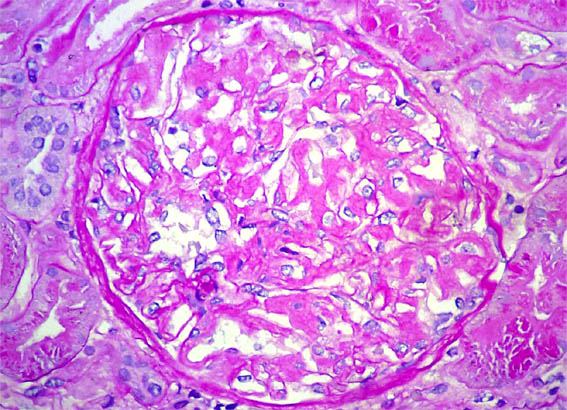

Figure 4.

Masson's

trichrome stain,

X400.